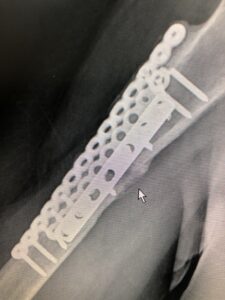

圖 2

再次回診後,加入「優偌肽」自體血小板裂解液凍晶進入療程,兩個月回診後,原本癒合不佳的患處已骨增生且逐漸癒合(圖二 鼠標箭頭處)。